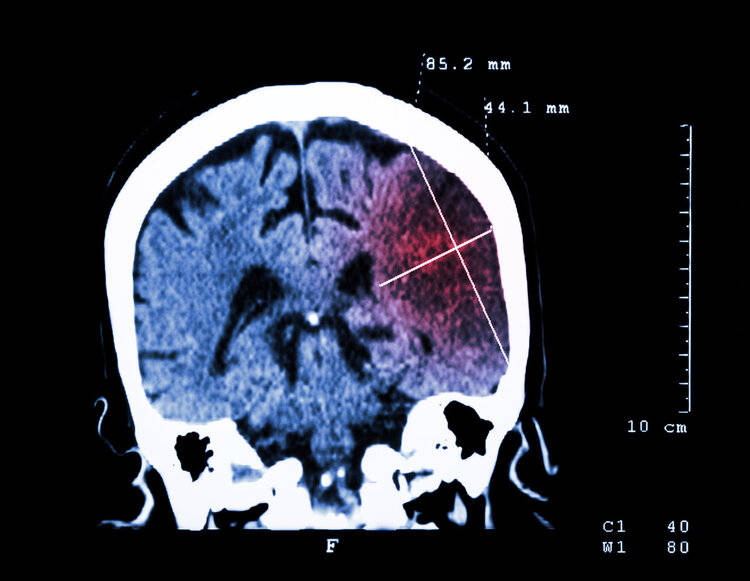

经检查大爷血压高达180mmHg,结合大爷有高血压病史,又出现口角歪斜、肢体无力等表现,最后诊断为脑出血,需要立刻手术降压。医生提醒这已经不是第一个因为高血压引发脑出血的病例了。

其实高血压长期对血管的冲击会让血管失去弹性,增加血管僵硬度,使得血管变得更加脆弱。尤其是脑血管在不稳定的血压影响下更容易出现破裂、阻塞等风险,随着脑血管壁持续增厚,管腔变窄,短期内血压的飙升会使得脑血管出现急性破裂或闭塞,脑卒中、脑出血也会随之而来。

如今,高血压已经是导致血管破裂的高危因素,而临床中近70%的脑出血都与高血压有关,而且别以为年轻人就不会得高血压,或者得了高血压也没事,要知道再年轻强壮的血管也耐不住天天的造。